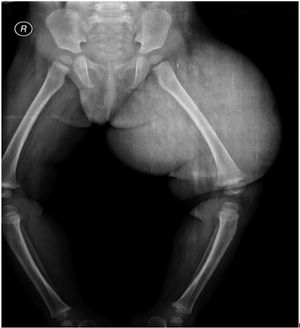

Case History: 2-year-old female with complaints of swelling of vulva, gluteal region, and left thigh since birth.